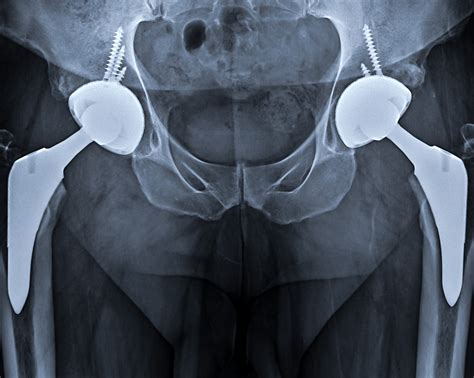

Post-Operative Monitoring

After the surgery, hip implant X-ray imaging is used to:

• Verify the correct placement and alignment of the implant.

• Detect any early signs of implant failure or complications.

• Monitor the healing process and bone integration.

Regular follow-up hip implant X-ray imaging helps ensure that the implant is functioning properly and that the patient is recovering as expected.

Long-Term Management

Over time, hip implants can wear out or become loose, leading to pain and reduced mobility. Long-term management involves regular hip implant X-ray imaging to:

• Assess the condition of the implant and surrounding bone.

• Identify any signs of wear, loosening, or infection.

• Determine the need for revision surgery.

Early detection of potential issues through hip implant X-ray imaging can prevent more serious complications and the need for additional surgeries.